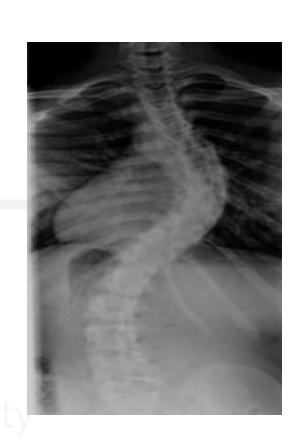

Which of the following is associated with this finding?

- Adolescent Idiopathic Scoliosis

A 14-year-old girl presented to the clinic after her parents noticed a deformity in her back. Adamโs test was positive. Which of the following pathologies represents this case?

- Idiopathic scoliosis

What is this deformity?

- Gibbus deformity

What is the deformity in this picture?

What is the most common cause?

- TB, congenital POTTS